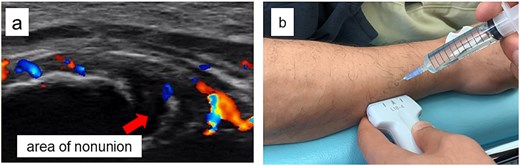

A 54-year-old man sustained a mid-diaphyseal ulnar fracture from a direct kick during karate practice. Initial conservative treatment at another hospital failed to achieve union over 12 months, and he was referred to our clinic with a diagnosis of nonunion. At presentation, he reported significant pain with a numerical rating scale (NRS) score of 6, and radiographs showed a 9 mm interfragmentary gap (Fig. 1a and b). Given his pain, we initiated proactive conservative management with prolotherapy, primarily targeting pain relief. Ultrasound revealed marked doppler signals at the nonunion site, suggesting inflammation and neovascularization. A mixture of 6 ml 50% dextrose and 4 ml 1% lidocaine (final 30% dextrose) was injected under ultrasound guidance into the neovascularized tissue and fracture gap (Fig. 2a and b). From the second session onward, bone healing had progressed to the point where the solution could no longer be injected between the bone fragments, so subsequent injections were administered around the periosteum. No restrictions were placed on weight-bearing or activity. Pain improved to NRS 4 at 2 weeks and to NRS 2 at 4 weeks, with early callus formation seen on radiographs. Prolotherapy was repeated five times at 2–3 week intervals. By 12 weeks, the patient was pain-free (NRS 0) and returned to karate. Radiographic union was confirmed at 15 weeks (Fig. 3a–d). Although initiated for pain control, prolotherapy led to relatively early bone union without surgery or complications.

Ultrasound findings and images during the procedure. (a) Ultrasound image at the start of treatment showing marked Doppler signals around the nonunion site. (b) Dextrose injection into the nonunion site under ultrasound guidance.